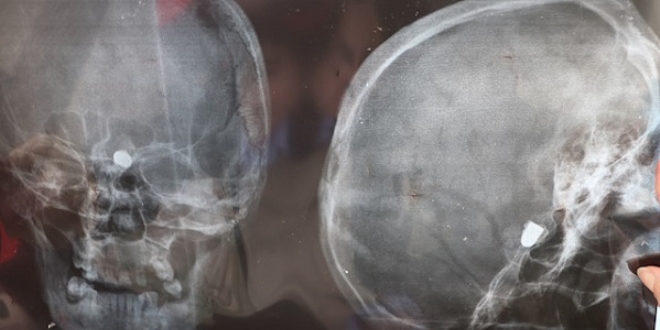

Kafası kanayan Çakmak, ağabeyi ile oynadığı sırada yaralandığını düşünen ailesi tarafından Trabzon'daki bir hastaneye götürüldü. Burada yapılan ilk müdahalenin ardından çekilen röntgen filminde kafasında mermi çekirdeği olduğu tespit edilen Çakmak, Ankara'daki hastaneye sevk edildi.

Kurşunun oluşturduğu tahribat dolayısıyla sol gözü görme yetisini kaybeden, sol kol ve bacağı da felç olan Çakmak, ameliyat edildi. Çakmak'ın kafasındaki mermi çekirdeği, hayati tehlike riski bulunduğu için çıkartılamadı.

Çakmak, kurşunun başının üst kısmından girdiğini ve sol gözünün arka bölümünde kaldığını anlatarak, "45 yıldır geçmeyen baş ağrısı ve uykusuzlukla mücadele ediyorum. Başım ağrıdığı için düzenli ağrı kesici alıyorum. Uyku sorunum var, yattığım zaman sanki biri kafama yumruk atıyormuş gibi acıyla sıçrayıp kalkıyorum. O nedenle de ancak uyku ilacı alarak uyuyabiliyorum" dedi.